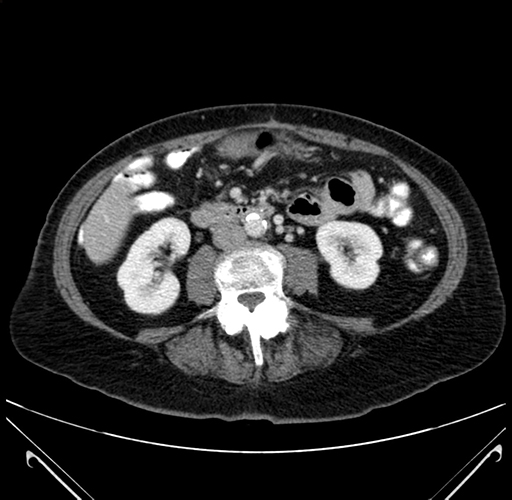

Axial Venous